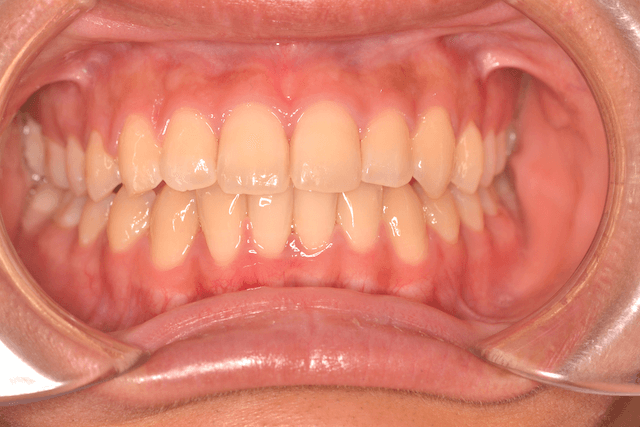

叢生を抜歯とDBSで改善した症例

※DBSとはダイレクトボンディングシステムと呼ばれており、ブラケットにワイヤーを通して歯を動かしていく矯正治療です。

患者情報

17歳女性

主訴

歯並びがガタガタ

行った治療内容

上下顎両側4番抜歯、DBS

治療のリスク

歯肉退縮、歯根吸収

治療期間

動的治療期間3年6か月

※ クリックして拡大することができます。